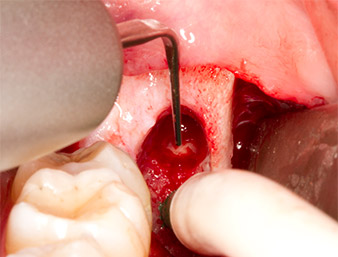

Using an instrument for periodontal debridement (Piezomed P1), the periodontal ligament space of the radix relicta was then widened minimally (Fig. 8).

The same activated instrument was inserted into the root canal and loosened the fragment as a result of its micro-oscillating vibrations (Fig. 9, 10).